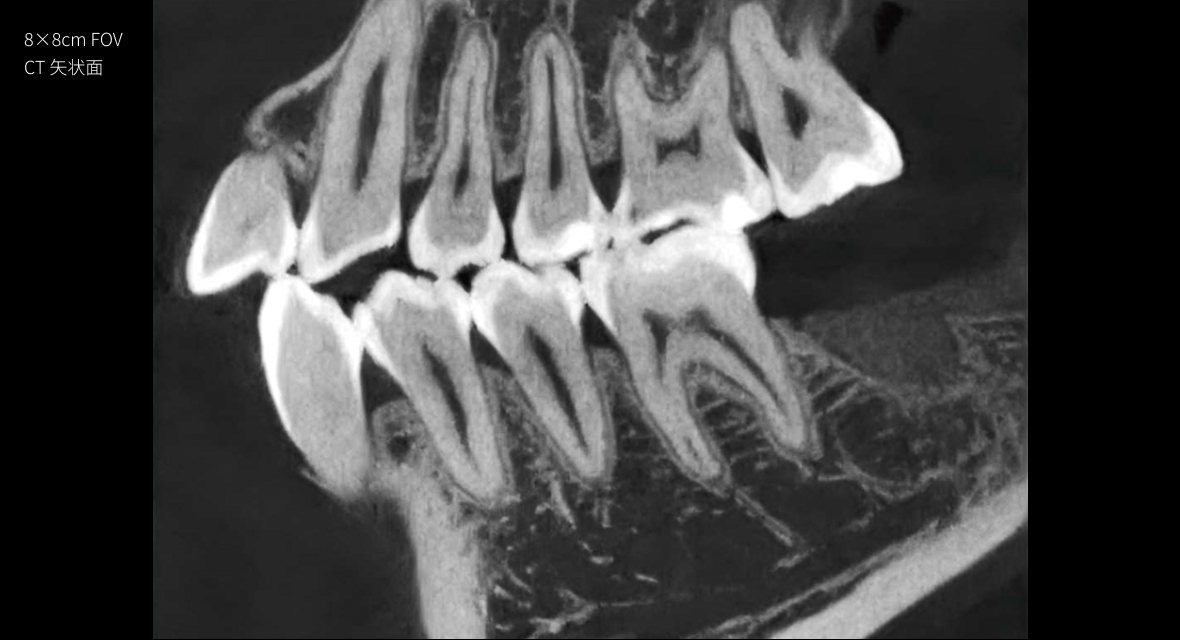

16×15cm

非拼接大视野

28lp/cm

高精准